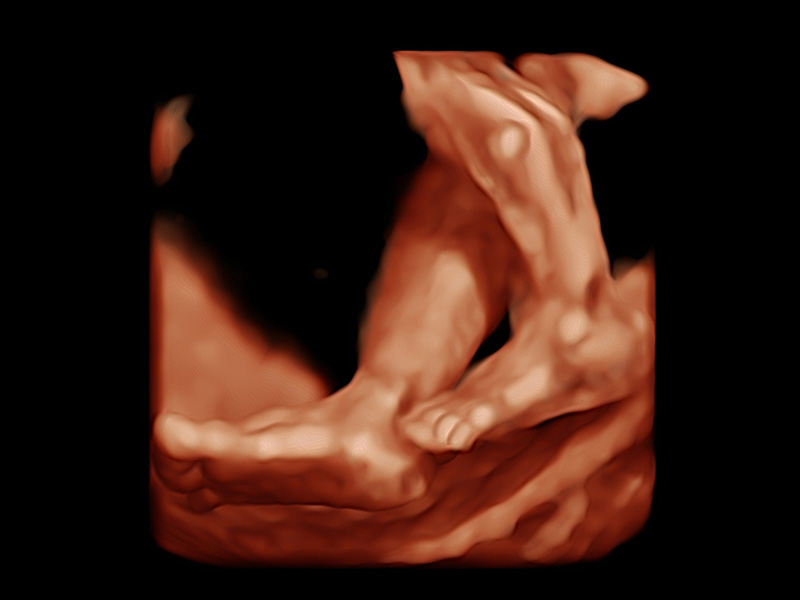

Smart 3D/4D

Einfach und effizient gemacht

Der neue High-Density-Volume-Rendering-Engine von P60 Exp optimiert signifikant die Signalverarbeitung und 3D-Rendering, was seine volumetrische Leistung in Bezug auf hohe Volumenraten, außergewöhnliche Details und realistische Effekte hervorhebt. Die umfassende Volumenbildgebungssuite erweitert Ihre diagnostischen Fähigkeiten in die nächste Ära der Bildgebung mit außergewöhnlicher Bildqualität und optimiertem Workflow.

• Fetale Finger mit 3D S-Live

• Fetaler Rücken mit FreeVue und VCI